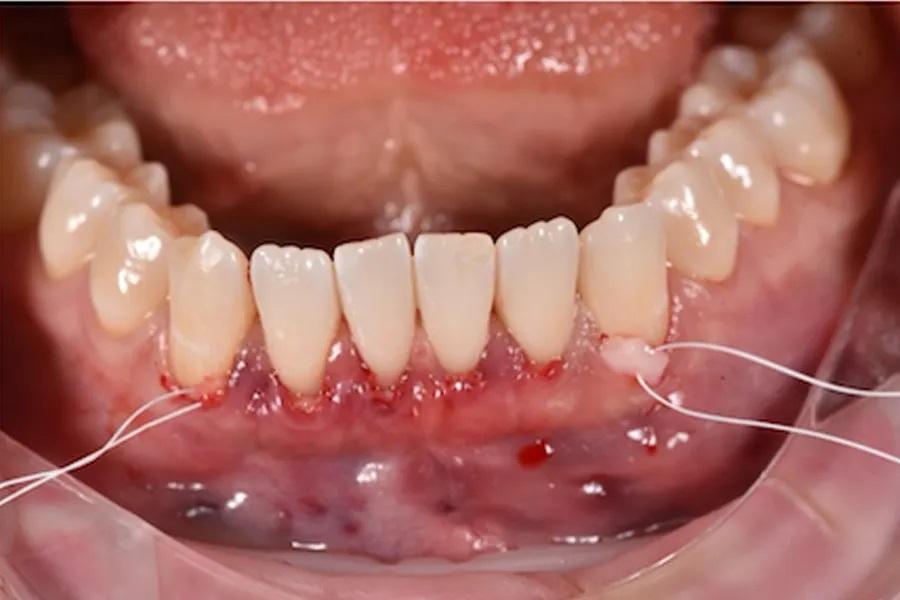

При тонком фенотипе с начальными рецессиями минимально инвазивная тоннельная техника с применением СТТ (при необходимости — с использованием эмалевых матриксных белков на оголенных корнях) позволяет увеличить толщину мягких тканей и обеспечить долгосрочную стабильность после ортодонтического перемещения зубов. (фото 13 – 16)

Фото 13. Закрытие рецессии с использованием СТТ, выполненное методом тоннелирования. Реципиентные участки были подготовлены с применением минимально инвазивной тоннельной техники с краевым разрезом без вертикальных релизных разрезов. Тоннель был расширен в межзубных промежутках для атравматичного введения трансплантата при сохранении целостности сосочков и оптимального кровоснабжения со стороны слизисто-надкостничного лоскута.